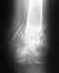

Подвернул ногу, есть перелом, нужен совет.

http://photofile.ru/express/indrarozatofanicorshtitha/Мужчина, 35 лет, подвернул ногу на бегу.Отёк от растяжения небольшой, спадает.Ничего не болит, если не двигать ногой.Нога сейчас в полужёсткой повязке.Что будет без хирургического вмешательства?Какое может быть хирургическое вмешательствов данном случае?Мне предлагают вставить металлический штырь на целый год.Какие ещё возможны варианты?